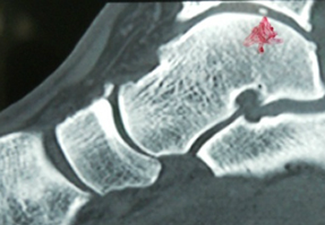

Imagenes:

Sindrome friccional óseo. Cuerpo libre intraarticular.